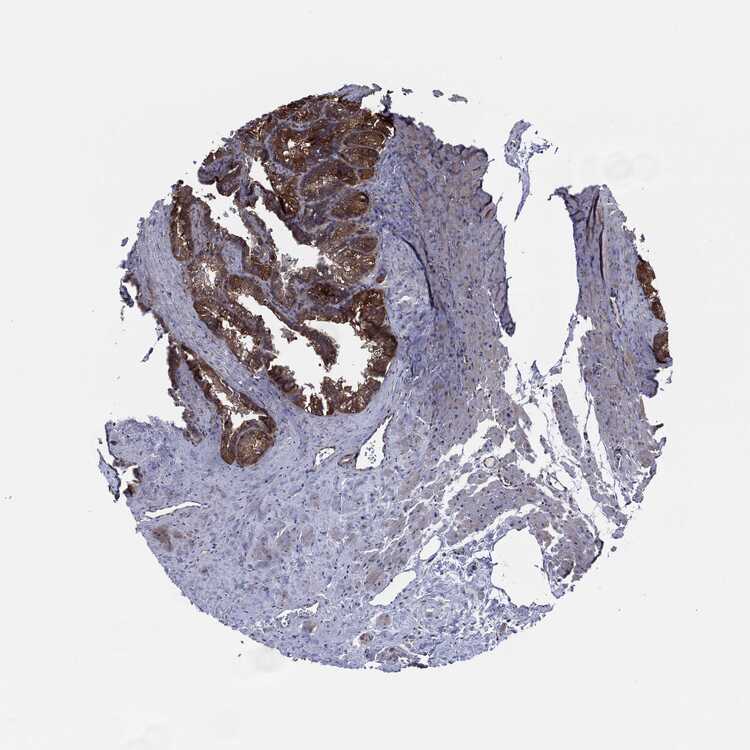

SEMINAL VESICLE - Antibody stainingi

Antibody staining in the annotated cell types in the current human tissue is reported as not detected, low, medium, or high, based on conventional immunohistochemistry profiling in selected tissues. This score is based on the combination of the staining intensity and fraction of stained cells.

Each image is clickable and will lead to virtual microscopy that enables deeper exploration of all samples and also displays staining intensity scores, fraction scores and subcellular localization as well as patient and tissue information for each sample.

Antibody HPA030419Antibody HPA030420Antibody HPA030422Antibody CAB025196Antibody CAB080286Antibody CAB080287

Glandular cells Not detectedNot detectedMediumMediumMediumMedium